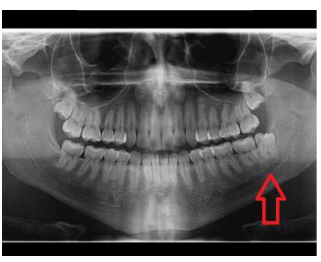

Analise a imagem abaixo e assinale a alternativa que corresponda à estrutura destacada.